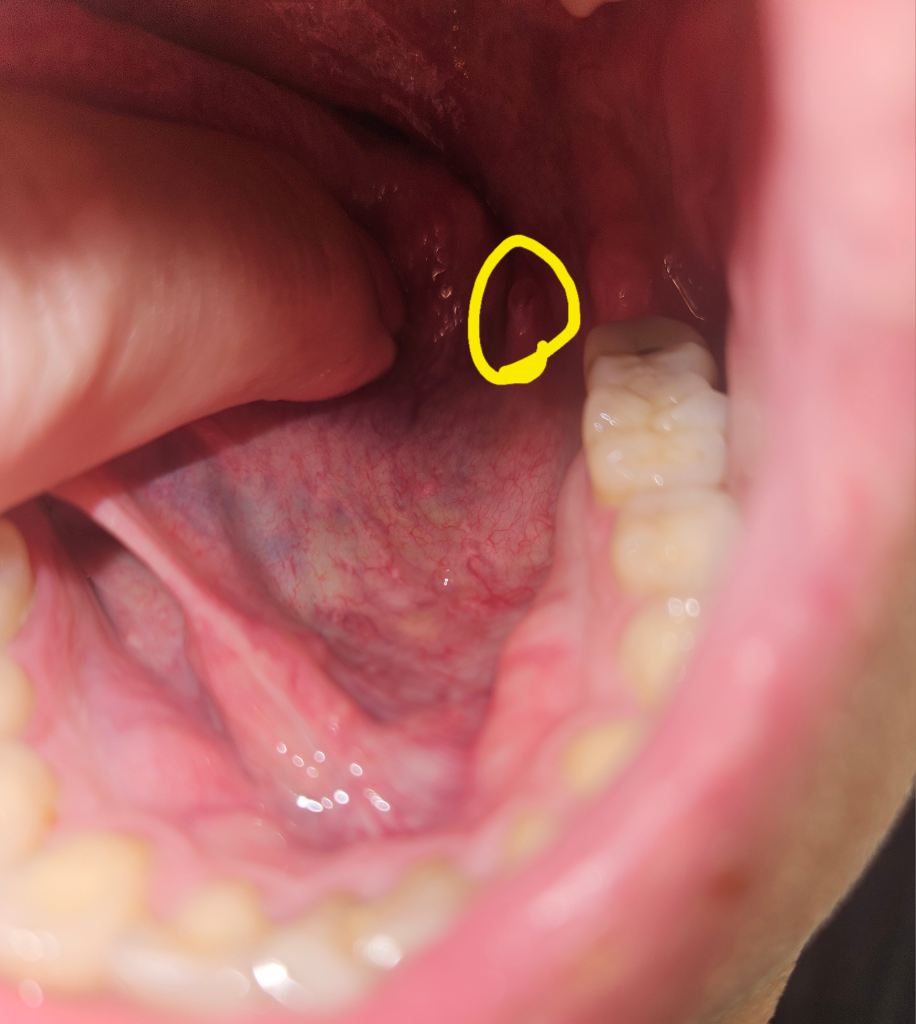

입안쪽 혀 왼쪽 깊숙한곳에 생각보다 조금 큰 돌기 같은것이 나서 몇일째 없어지질 않고 있는데 병명을 알수있을까요? 병원을가야한다면 무슨과로 가야할까요?

• 1번 째 사진